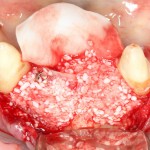

сделать операции синуслифтинга с двух сторон:

на фотографии, кстати, редкий случай многокамерной пазухи, с перегородкой посередине. В подобных ситуациях синуслифтинг, хоть и получается сложнее, но все равно осуществим.

сделать остеопластику там, где это требовалось: